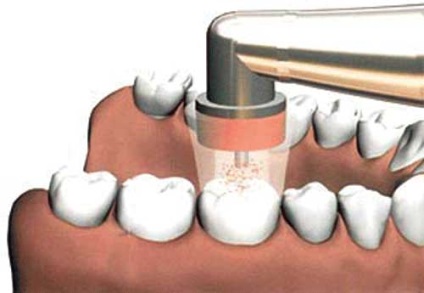

Sok fogorvos fogszuvasodás kezelésére levegővel súrolószerrel módszer. Ha el szeretné távolítani, szuvas betétek orvos egy speciális eszköz, a működési elve emlékeztet homokfúvó. De ahelyett, homok alatt a nyomás a sűrített levegő vagy gáz keresztül apró tip szolgál koptató szemcsék szilícium vagy alumínium-oxid. Néha szolgált a szokásos keverék szódabikarbóna.

Az elv a kezelés légáramszitálás

Takarmány részecskék szerinti berendezéssel előállított eléri a felületet az érintett fogat és tisztítsa meg fogszuvasodás befolyásolása nélkül az egészséges részek. szuvas betétek repül ki részecskéket szar egy speciális eszköz. A kezelés után a fogak lezárjuk és polírozott.

Légi koptatás következtében a fogak teljesen biztonságos, ugyanakkor, hogy megakadályozza a részecskék bejutását a szembe, a fogorvos munka közben szükséges viseljen védőszemüveget. Továbbá, az orvos meg kell védeni műveletlen területeken a szájüregben. Erre a célra is alkalmaz közgát vagy okoz légmentes Lábszárvédõk a szomszédos fogak és az íny.

Az előnyök a levegő-koptató módszer, hogy a fűtés a sérült fogszövetekkel, rezgés és a nyomás nem áll rendelkezésre, hogy szükség van a érzéstelenítés csökkent, a kockázat a mikrorepedések minimális. Ezután gyengéd kezelése a fog felülete száraz marad, ezáltal beállítása egy erős tömítést. Ez egy egyszerű és gyors eljárás, amely lehetővé teszi a betegek kezelésére több foga egy látogatás a fogorvos.

A hátrányok a levegő-csiszoló kezelés egy magasabb fogak érzékenységét. Ha a beteg fájdalmat érez, a sérült terület kell érzésteleníteni. Az anesztézia és érzéstelenítők lehet tanulni „hogy a kezelendő fogszuvasodás fáj” a cikket. Amellett, hogy gyógyítani mély szuvasodás ily módon lehetetlen.